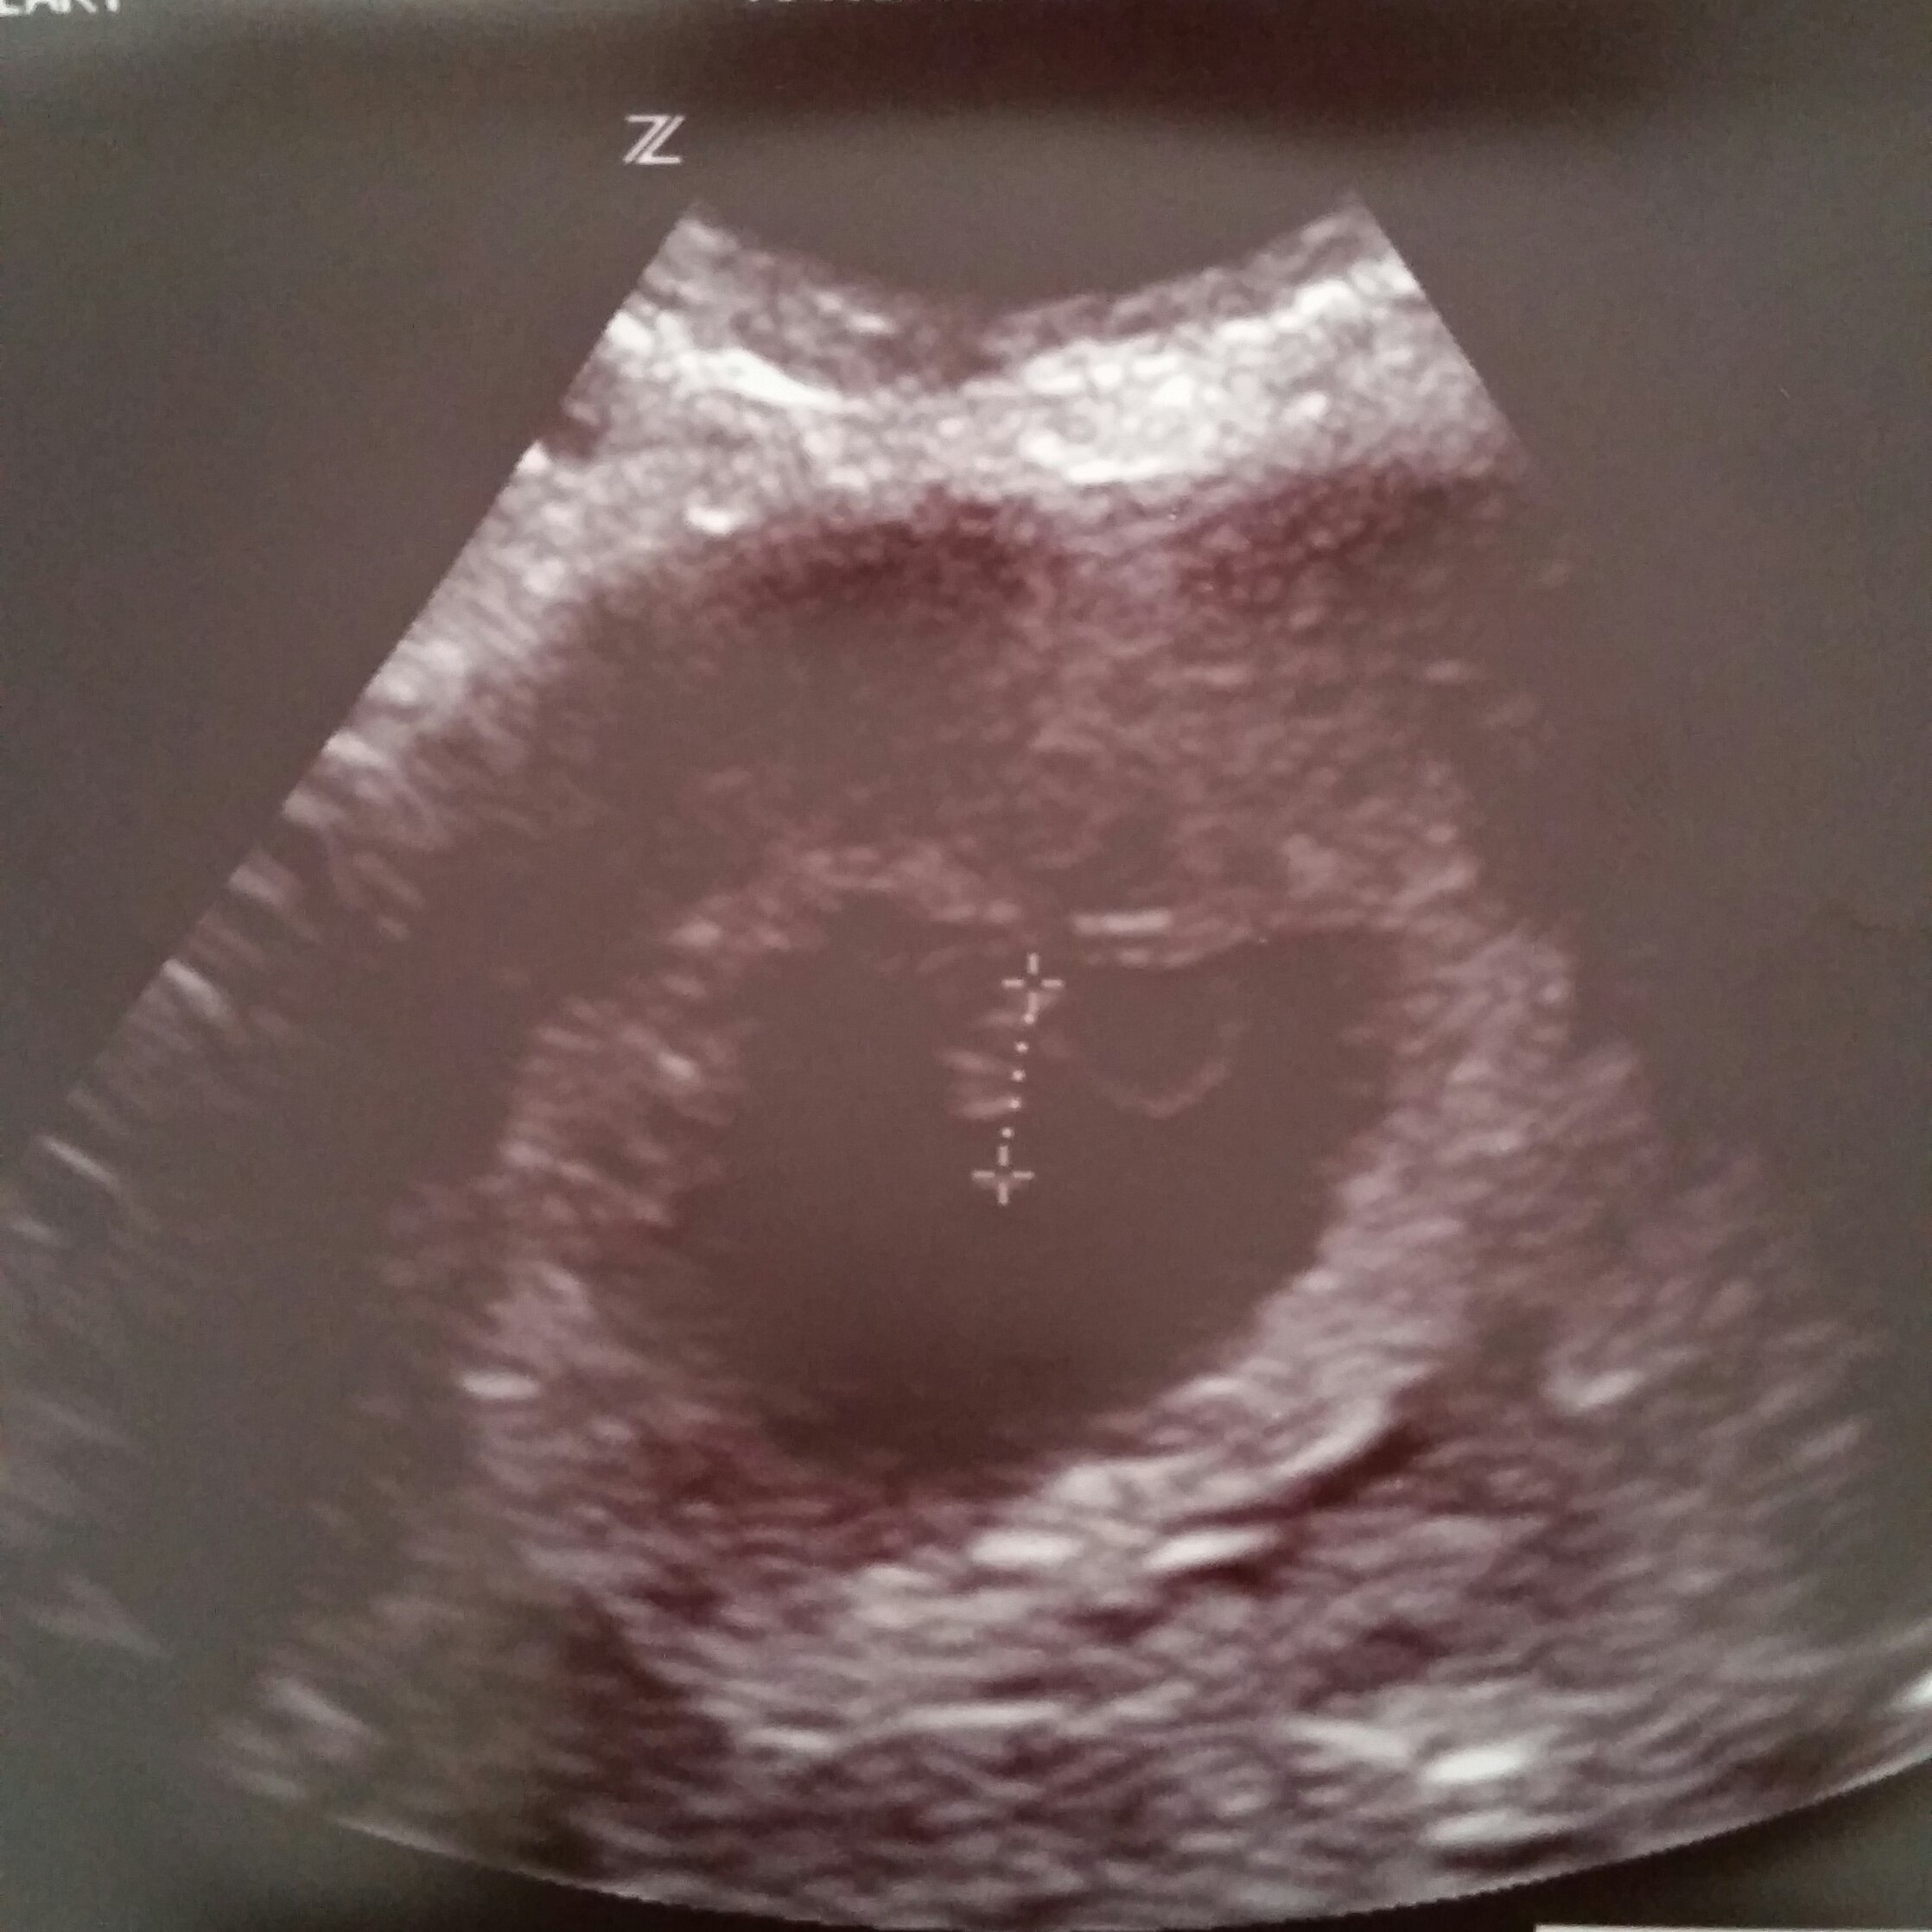

Anyone else get an abdominal ultrasound for their first?

EDD: 15th Feb 2016

125 bpm

Thought i was further along.. Had a early scan because i had an mc 2 months ago.

Next week follow up to see if she/he has grown. Nervous!